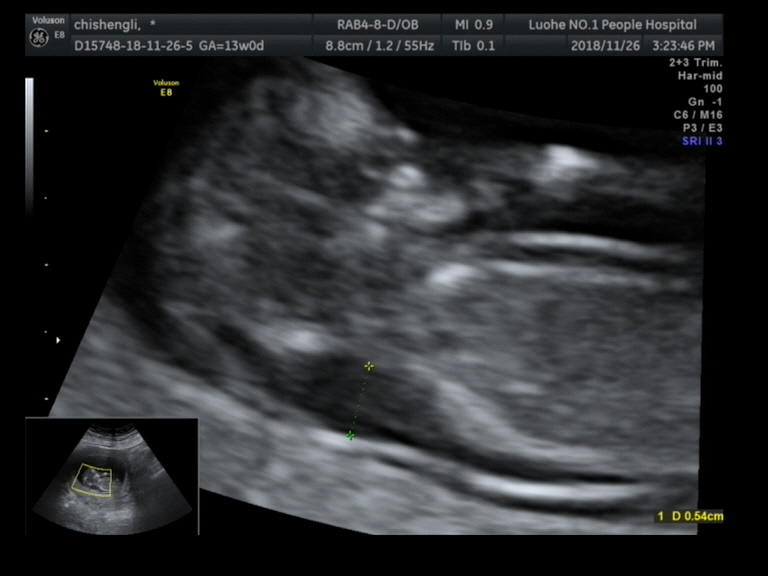

宫腔内可见一胎儿回声,颅骨光环可显示。

双顶径:17mm,头臀长:50mm, 胎动胎心好,胎心率:158次/分,

羊水最深值:33mm,胎盘附着于子宫前壁,厚:12mm, NT:5.4mm.

胎儿颈背部可见一20mmx6.7mm的囊性回声,内可见多条线样高回声分隔,呈多房状改变,CDFI:其内未见明显血流信号。

四腔心切面隐约可见,室间隔上部回声缺失约1mm,静脉导管频谱未见明显异常。